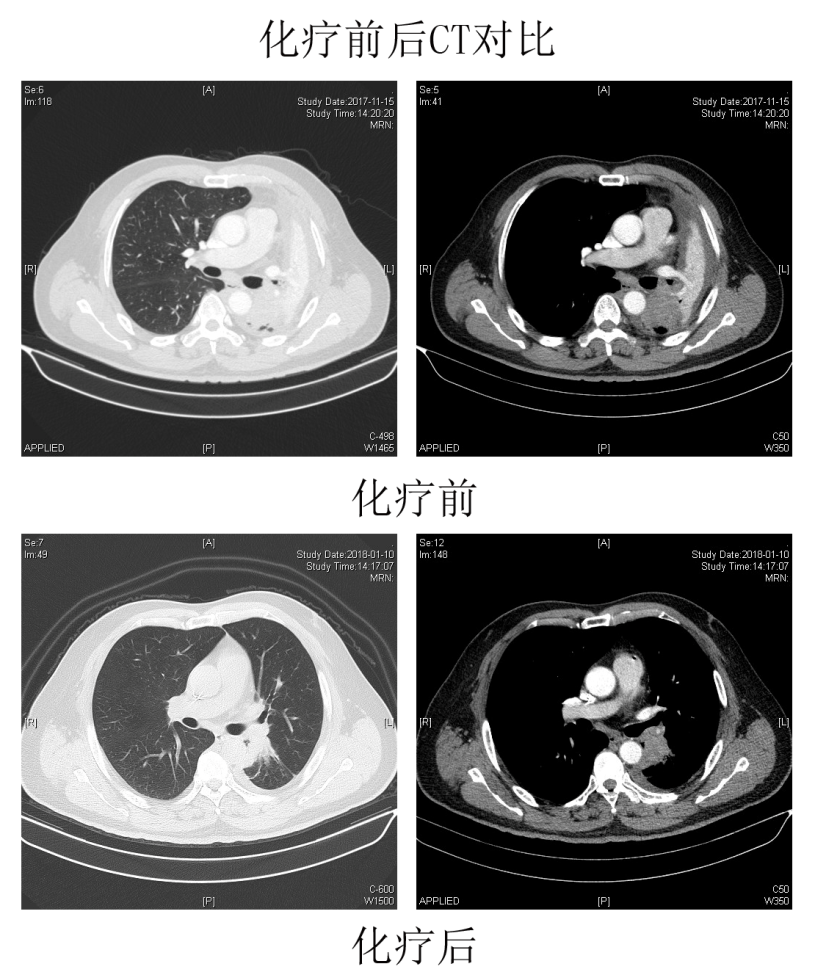

医院肺部肿瘤诊疗中心多学科(MDT)团队经过讨论,为老王制定了个体化治疗方案:术前新辅助化疗2周期后,由胸外科潘小杰主任医师团队实施单操作孔胸腔镜左全肺切除+系统性淋巴结清扫术。